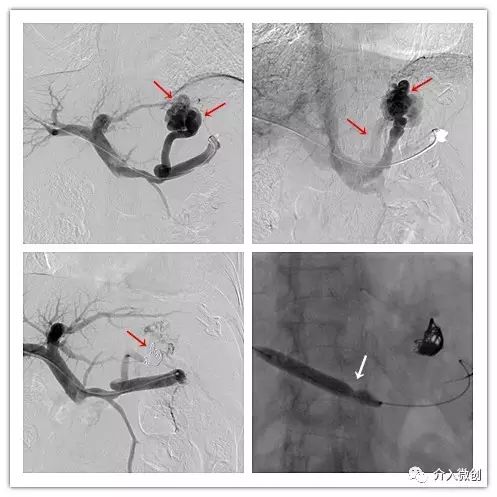

- 经皮肝穿门静脉造影示孤立性胃底静脉曲张,胃-肾分流;应用弹簧钢圈及泡沫硬化剂闭塞分流血管;应用球囊导管扩张局限性狭窄的脾静脉。